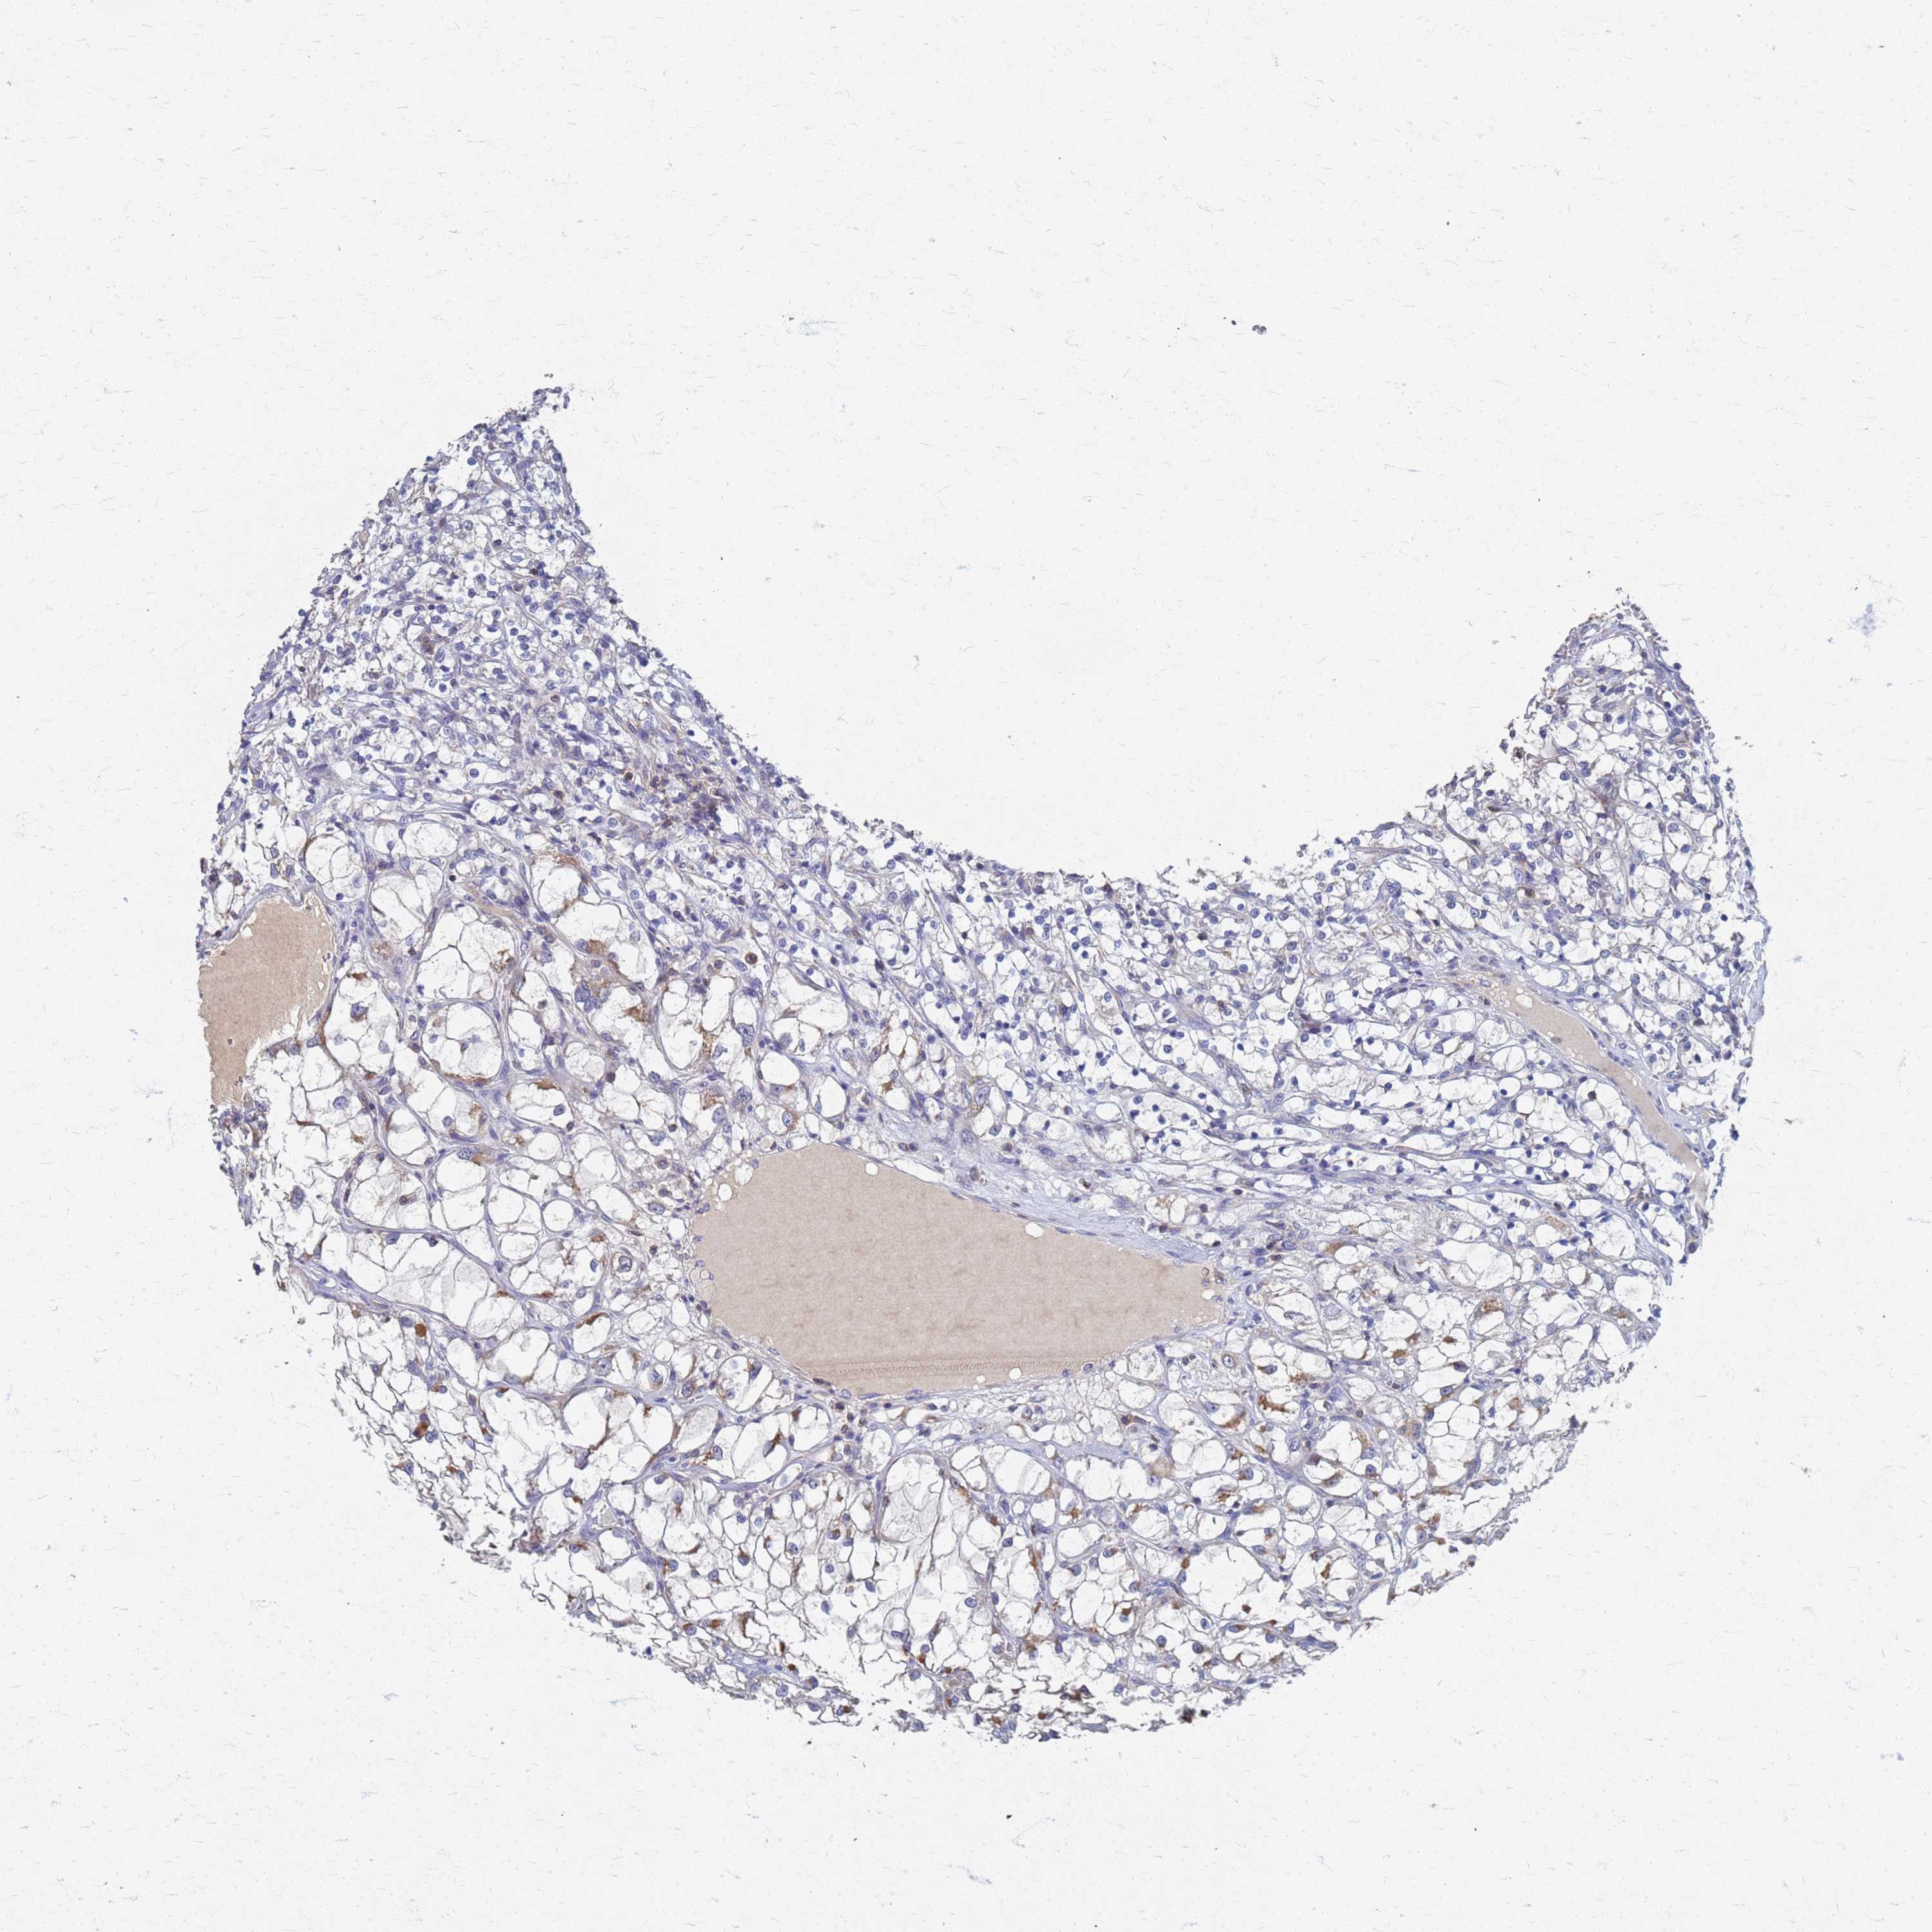

KIDNEY RENAL CLEAR CELL CARCINOMA (VALIDATION) - Interactive survival scatter ploti

The Survival Scatter plot shows the clinical status (i.e. dead or alive) for all individuals in the patient cohort, based on the same data that underlies the corresponding Kaplan-Meier plots. Patients that are alive at last time for follow-up are shown in blue and patients who have died during the study are shown in red.

The x-axis shows the expression levels (FPKM) of the investigated gene in the tumor tissue at the time of diagnosis. The y-axis shows the follow-up time after diagnosis (years). Both axes are complimented with kernel density curves demonstrating the data density over the axes. The top density plot shows the expression levels (FPKM) distribution among dead (red) and alive patients (blue). The right density plot shows the data density of the survived years of dead patients with high and low expression levels respectively, stratified using the cutoff indicated by the vertical dashed line through the Survival Scatter plot. This cutoff is automatically defined based on the FPKM cutoff that minimizes the p-score. The cutoff can be changed by dragging the vertical line or by entering a cutoff value in the square labeled "Current cut-off".

Under the Survival Scatter plot the p-score landscape (black curve; left axis) is shown together with dead median separation (red curve; right axis). Dead median separation is the difference in median mRNA expression between patients who have died with high and low expression, respectively. It is calculated as follows: median FPKM expression of dead patients with high expression - median FPKM expression of dead patients with low expression. This is intended to aid the user in visually exploring custom cutoffs and the associated p-scores and dead median separation.

Individual patient data is displayed and can be filtered by clicking on one or more of the category buttons on the top of the page. Categories describing expression level and patient information include: high, low, alive, dead, female, male and tumor stages. The scale of the x-axis can be toggled between linear and log-scale by clicking on the "x log" button. Mouse-over function shows TCGA ID, patient information and mRNA expression (FPKM) for each patient.

& Survival analysisi

Kaplan-Meier plots summarize results from analysis of correlation between mRNA expression level and patient survival. Patients were divided based on level of expression into one of the two groups "low" (under cut off) or "high" (over cut off). X-axis shows time for survival (years) and y-axis shows the probability of survival, where 1.0 corresponds to 100 percent.

KRCC1 is not prognostic in Kidney Renal Clear Cell Carcinoma (validation)

Best expression cut offi

: 29.42

Median expressioni

: N/A

Median follow up timei

P scorei

N/A

5-year survival highi

For melanoma and glioma, 3-year survival is shown.

5-year survival lowi

TCGA RNA samplesi

RNA-seq data is reported as average FPKM (number Fragments Per Kilobase of exon per Million reads), generated by the The Cancer Genome Atlas (TCGA) .

Normal distribution across the dataset is visualized with box plots, shown as median and 25th and 75th percentiles. Points are displayed as outliers if they are above or below 1.5 times the interquartile range. FPKM values of the individual samples are presented next to the box plot.

Average pTPM 37.4

Number of samples 100